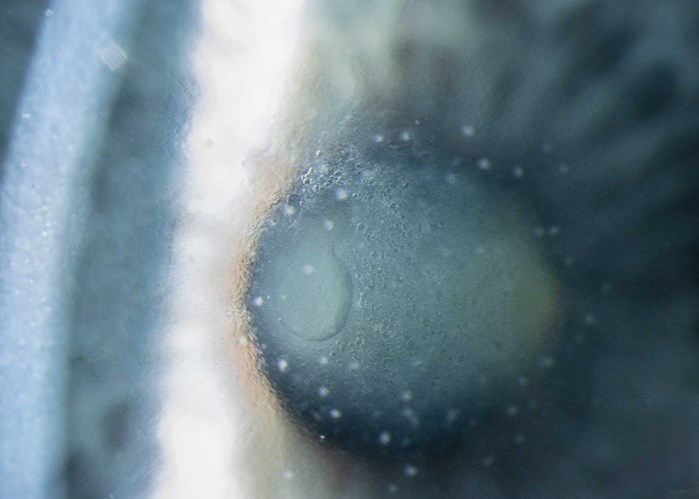

'Iris Flocculus' by Robert Hancock, Specialist Ophthalmic Photographer, Wirral University Teaching Hospitals, UK.